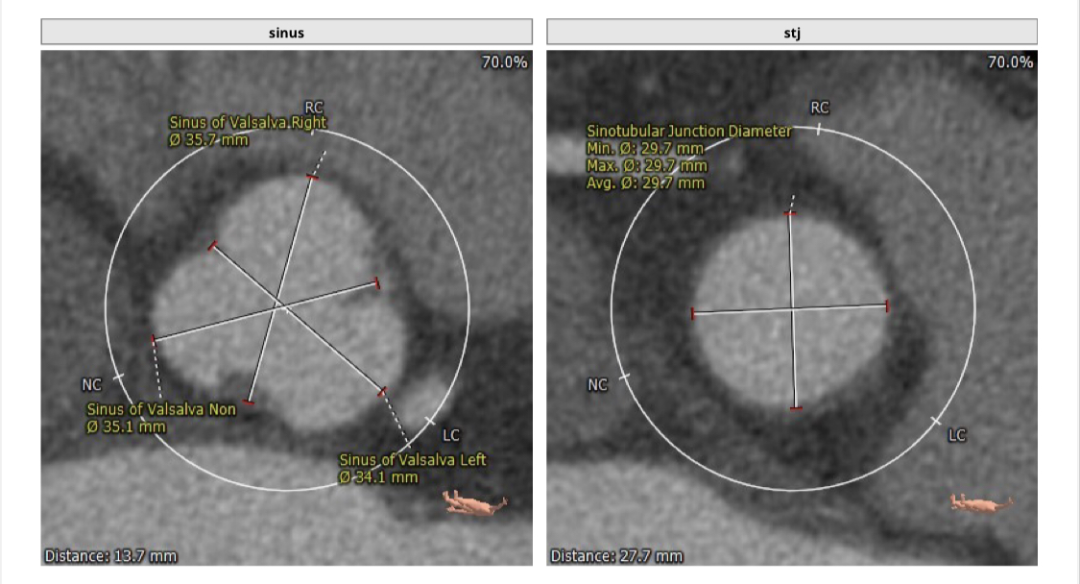

瓣环平均直径:27.0 mm,左室流出道平均直径:26.8 mm。

左冠高度:18.3 mm,右冠高度:17.1 mm。

患者为三叶瓣,主动脉瓣关闭不全,既往有二尖瓣生物瓣置换手术史,主动脉根部与二尖瓣夹角为127°,角度上不影响TAVR手术(大于120°较佳,小于100°有风险);法式窦及STJ结构尚可,升主动脉未见增宽,心脏角度尚可,左室大小明显增大。